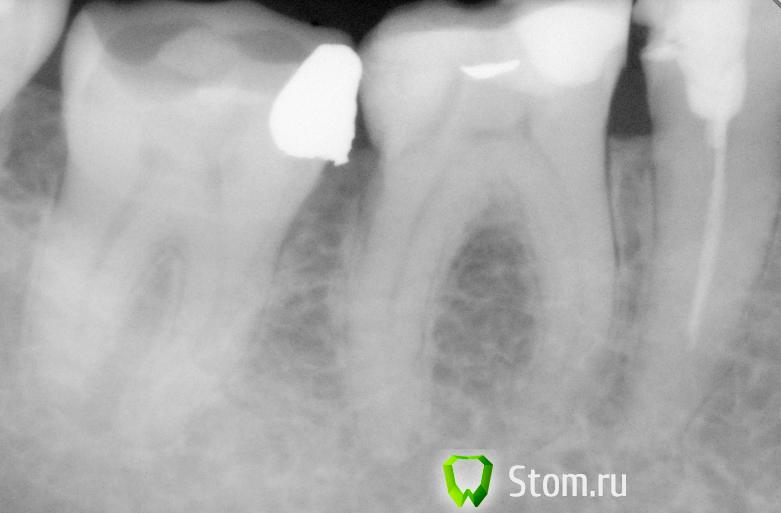

Ferny Опубликовано 9 декабря, 2011 Поделиться Опубликовано 9 декабря, 2011 Ув. коллеги, помлгите пожалуйста! Вот такой случай: Пац. жалуется на тупую ноющую боль в нижней правой шестёрке, которая возникает во время жевания какого либо твёрдого куска пищи, боль сама проходит в течение 20 минут. Пац. говорит что помогает паста Sensodyne и боль проходит. На 46 зубе стоит большая пломба с жевательной поверхности а так же с букальной на шейке зуба тоже небольшая пломба имеется, немного дефектная. Есть небольшая атриция бугорка. На верхней челюсти стоит мостПеркуссия немного болезненная, когда нажимаю на зуб 46 , то она чувствует болезненность, так же зуб 45 тоже реагирует на перкуссию. Пальпация в области верхушки корня безболезненна. Она раньше обращалась с этой проблемой к другим стоматологам, но ей не делали рентген и говорили что всё нормально и немного стачивали пломбу. В обычном положении когда зубы вместе её ничего не беспокоит. 1) Вот рентген, скажите ваши мнения по поводу зуба 46 и 45. 2) и ещё второй снимок зуба с кариесом на зубе 26 (другой пац). Опыта у меня мало, так что не знаю точно, звала старших коллег чтоб посмотреть, так они не нашли вобще ничего и сказали дырки нет, я сделала рентген и увидила что есть.Кариес уже в дентине? тоисть надо срочно делать? Спасибо заранее =) Ссылка на комментарий

Каплан Опубликовано 9 декабря, 2011 Поделиться Опубликовано 9 декабря, 2011 45 - ретрит + замена пломбы (вкв+коронка?)46- замена пломб (нет контакта с 45)47 замена пломбы (нависающий край) Ссылка на комментарий

ger_berra Опубликовано 9 декабря, 2011 Поделиться Опубликовано 9 декабря, 2011 Будьте готовы к тому,что в 46 не исключён хронический пульпит и ,соответственно,эндодонтия.Пациента обязательно предупредите.В остальном соглашусь с Капланом. Ссылка на комментарий

д-р Вит Опубликовано 9 декабря, 2011 Поделиться Опубликовано 9 декабря, 2011 46 нуждается в эндо,возможная причина боли трещина Ссылка на комментарий

Kivilgar Опубликовано 9 декабря, 2011 Поделиться Опубликовано 9 декабря, 2011 46 нуждается в эндо,возможная причина боли трещина+1 Ссылка на комментарий

DokDent Опубликовано 9 декабря, 2011 Поделиться Опубликовано 9 декабря, 2011 Будьте готовы к тому,что в 46 не исключён хронический пульпит и ,соответственно,эндодонтия.Пациента обязательно предупредите.В остальном соглашусь с Капланом. +1. Ссылка на комментарий

Elenushka Опубликовано 10 января, 2012 Поделиться Опубликовано 10 января, 2012 на 6 ке как будто виднеется пломба поставленная на рог пульплы... когда зуб лечен? возможно полечили по кариесу... под анестезией сосуды сужены не было видно сосудистно-нервоного пучка... Ссылка на комментарий

samsonov Опубликовано 10 января, 2012 Поделиться Опубликовано 10 января, 2012 на 6 ке как будто виднеется пломба поставленная на рог пульплы... когда зуб лечен? возможно полечили по кариесу... под анестезией сосуды сужены не было видно сосудистно-нервоного пучка...Доктор, Вы уверены ,что :1.нижний 6 всегда лечат под инфильтрационной анестезией с применением вазоконстрикторов?2.2х-мерный снимок достоверно показывает контакт полости с пульпарной камерой? Ссылка на комментарий